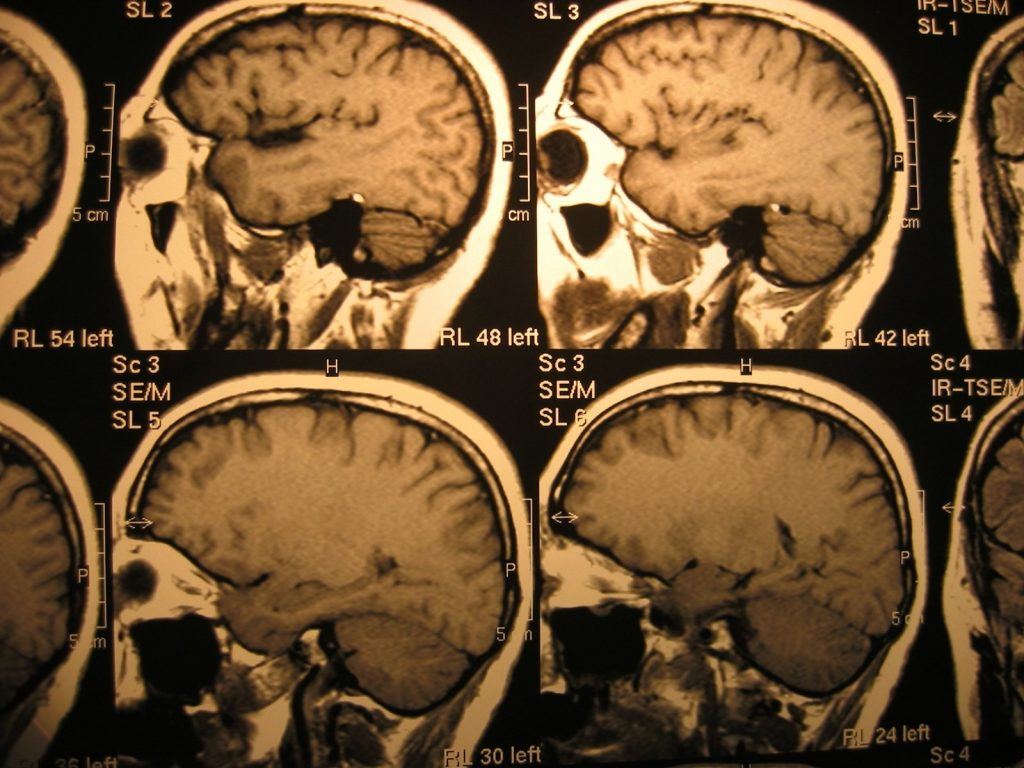

Traumatic brain injuries are typically caused by sudden, severe impacts to the head. The resulting injuries are often life altering because they result in permanent physical and mental trauma, leaving the victim with permanent disability, impaired functions and in need of long-term care and rehabilitation. Additionally, both the victims of traumatic brain injuries and their family members face significant monetary costs in having to pay for medical bills and other expenses associated with these serious injuries.

There are different degrees of traumatic brain injuries, based on how you were injured and what caused your accident. Additionally, the symptoms of these injuries may differ depending on the exact location where the brain was damaged. While complications associated with a traumatic brain injury may range from mild to severe, there are certain symptoms that are common to this type of injury, including: